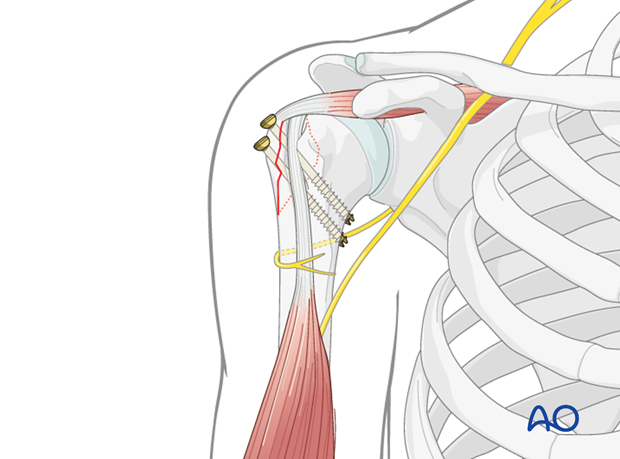

This image demonstrates the drilling of the pilot hole for screw insertion after reduction and temporary fixation.

This image shows the measurement of screw length after drilling, ensuring appropriate purchase without violating the articular surface.

This image illustrates the final screw insertion, providing stable fixation of the greater tuberosity fragment.

This is likely a fluoroscopic image demonstrating optimal screw placement, confirming that the screws are entirely within the bone and not penetrating the joint.

- Suture Augmentation: In cases of comminution, osteoporotic bone, or when concomitant rotator cuff repair is performed, suture augmentation can be used in addition to screws. Sutures can be passed through the rotator cuff insertion on the GT and secured to the humeral shaft, providing additional rotational stability and compression.